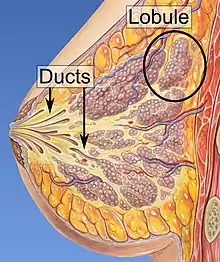

| Ducts of the mammary gland, the location of ductal carcinoma | |

Ductal carcinoma in situ (DCIS), also known as intraductal carcinoma, is a pre-cancerous or non-invasive cancerous lesion of the breast.[1][2] DCIS is classified as Stage 0.[3] It rarely produces symptoms or a breast lump one can feel, typically being detected through screening mammography.[4][5] It has been diagnosed in a significant percentage of men (see male breast cancer).[6]

In DCIS, abnormal cells are found in the lining of one or more milk ducts in the breast. In situ means "in place" and refers to the fact that the abnormal cells have not moved out of the mammary duct and into any of the surrounding tissues in the breast ("pre-cancerous" refers to the fact that it has not yet become an invasive cancer). In some cases, DCIS may become invasive and spread to other tissues, but there is no way of determining which lesions will remain stable without treatment, and which will go on to become invasive.[7] DCIS encompasses a wide spectrum of diseases ranging from low-grade lesions that are not life-threatening to high-grade (i.e. potentially highly aggressive) lesions.

Ductal carcinoma in situ (DCIS) literally means groups of "cancerous" epithelial cells which remained in their normal location (in situ) within the ducts and lobules of the mammary gland.[14] Clinically, it is considered a premalignant (i.e. potentially malignant) condition,[15] because the biologically abnormal cells have not yet crossed the basement membrane to invade the surrounding tissue.[14][16] When multiple lesions (known as "foci" of DCIS) are present in different quadrants of the breast, this is referred to as "multicentric" disease.[8]